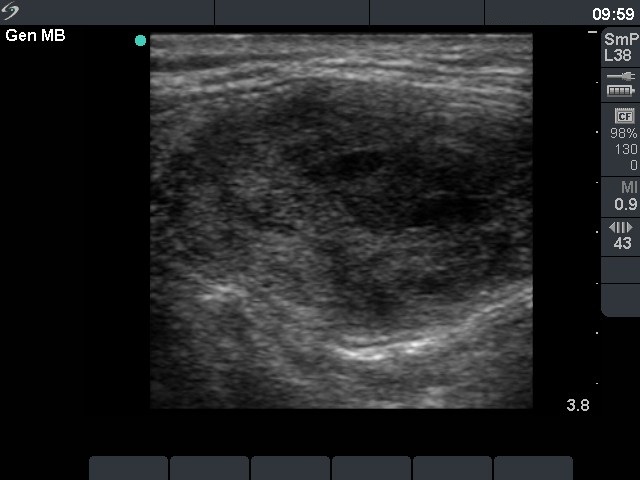

Ultrasonography : the thyroids were echonormal. There was a cystic nodule with an echonormal solid part in the right lobe.

Five sessions of sclerotherapy were performed. We gave 19.8 mL alcohol during five sessions of ethanol sclerotherapy. We demonstrate the first and the third sessions.